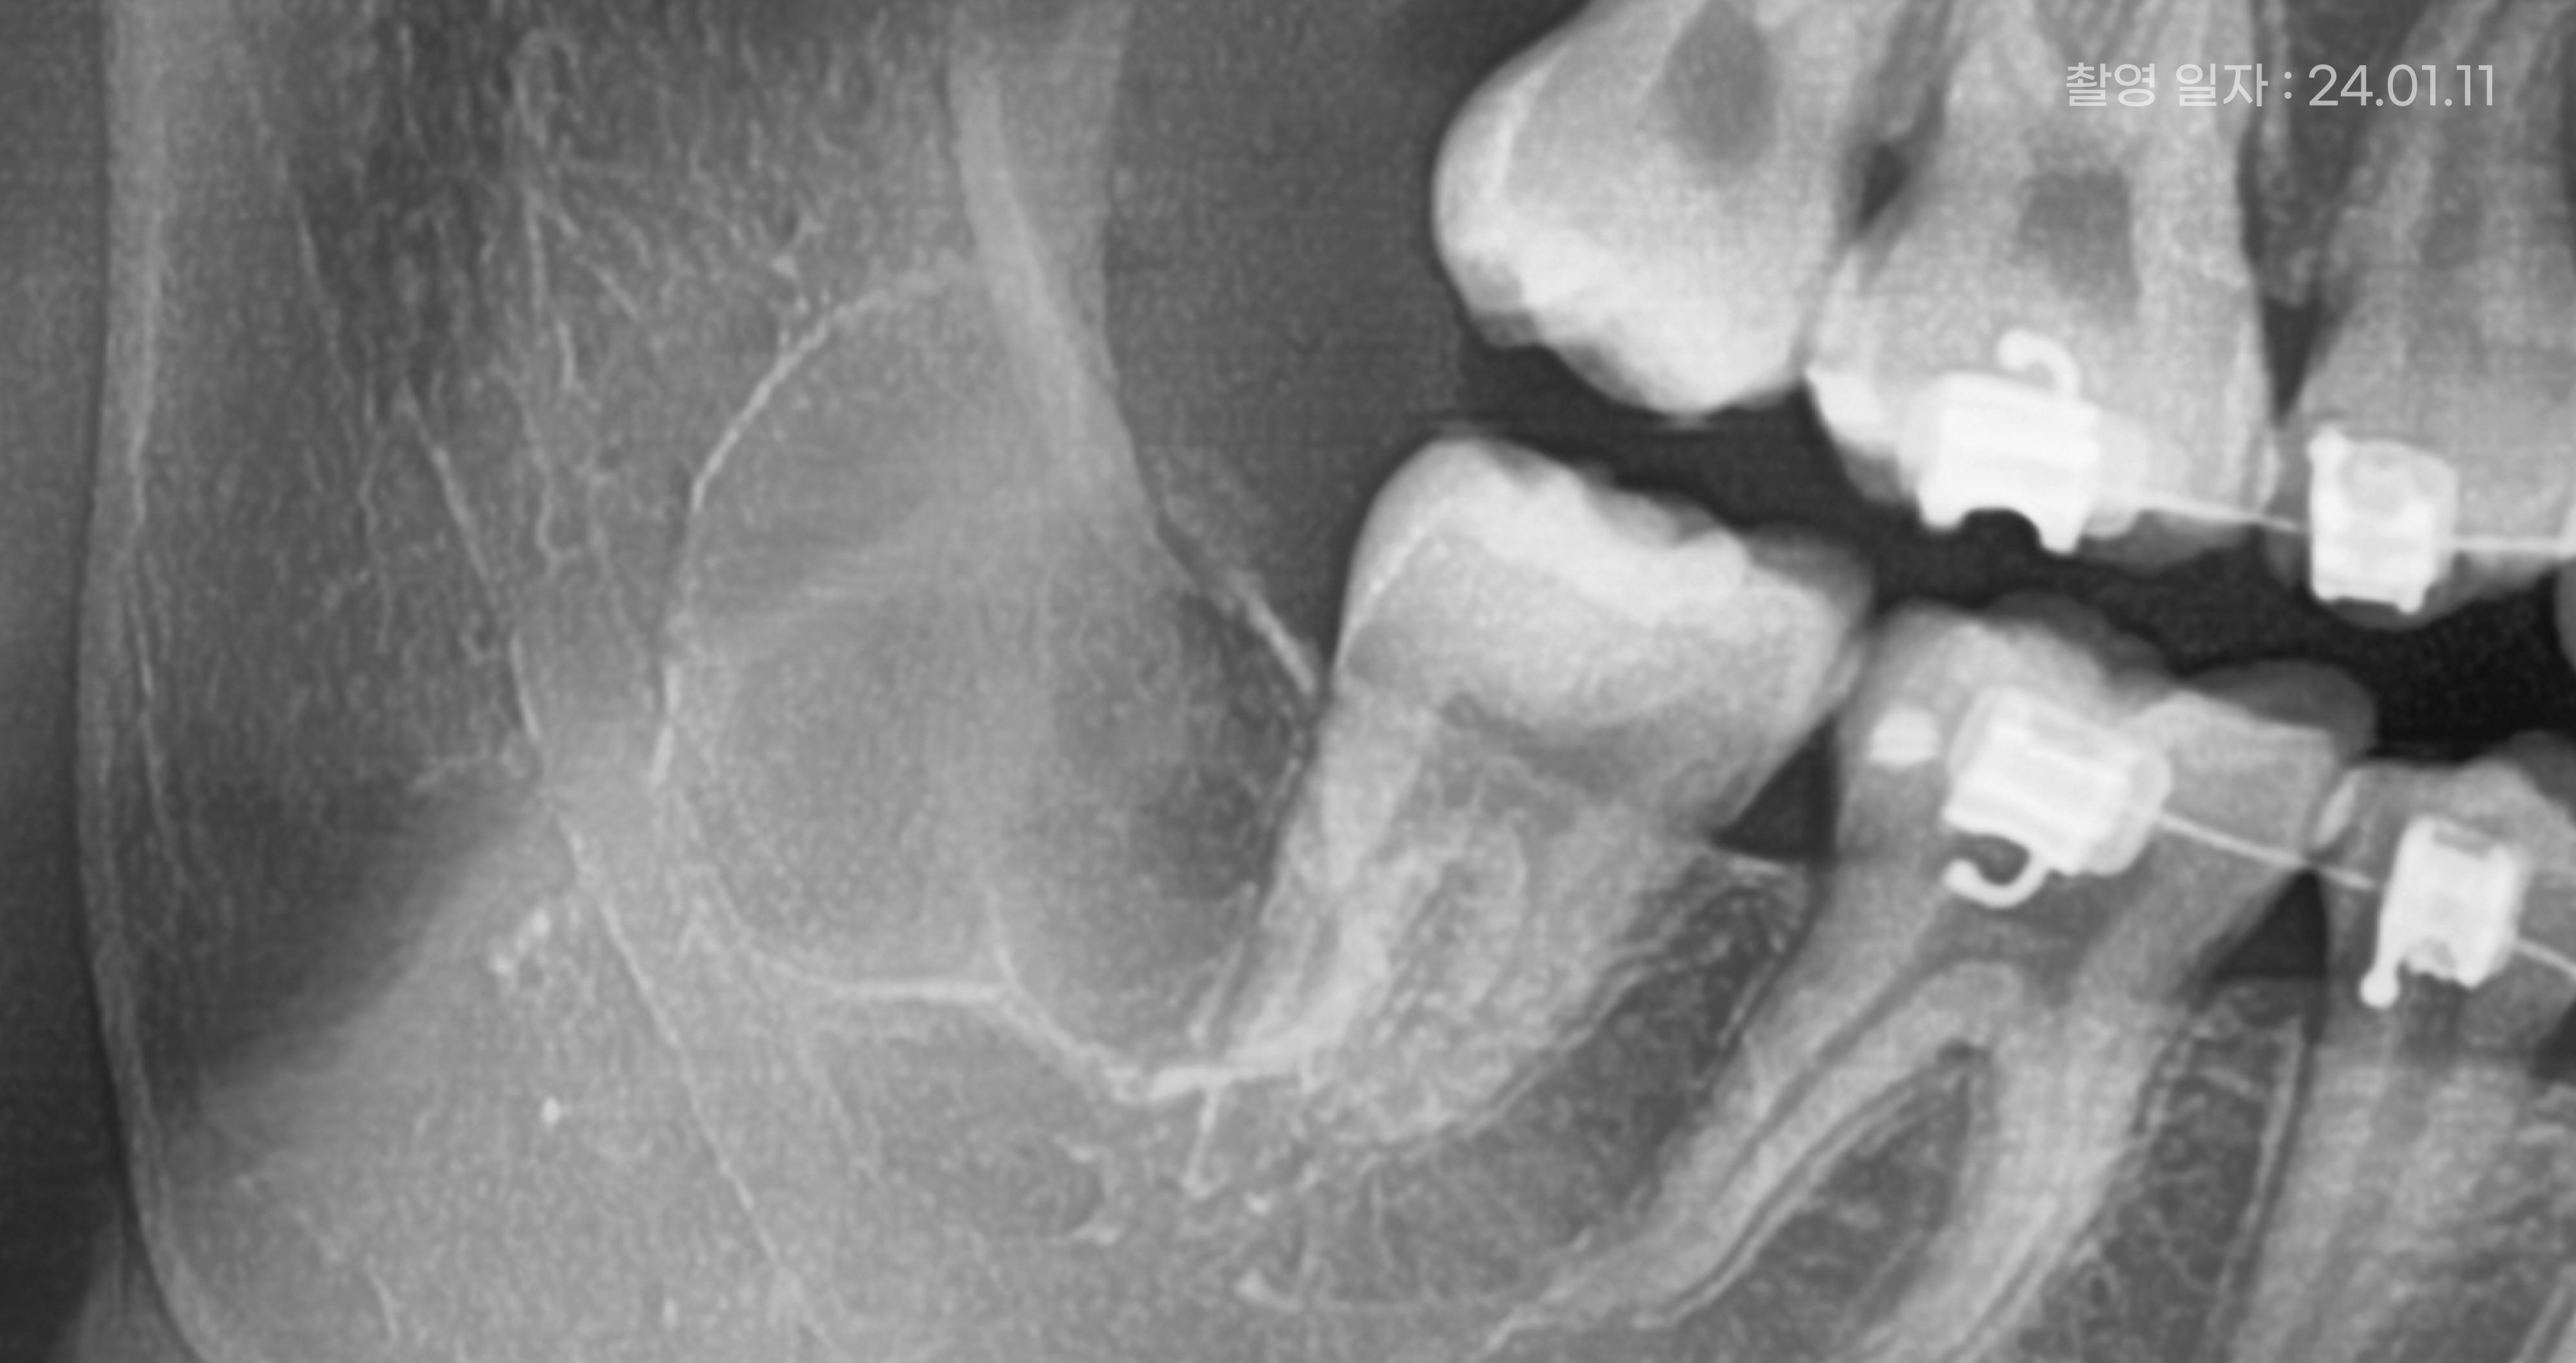

<매복사랑니 발치 후 예시 사진>

매복사랑니 발치 붓기 회복 기간

매복사랑니 발치 후 붓기는

일반 사랑니 발치 후 붓기에 비해

조금 더 길어질 수 있는데요.

개인마다 차이가 있지만,

보통 3~7일정도 지속될 수 있습니다.